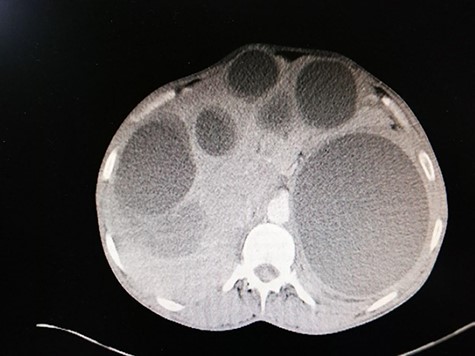

Abdominal ultrasound delineated multiple cystic lesions in the liver and the spleen. Computed tomography (CT) scan showed up to six rounded homogenous low-density cysts in both lobes of the liver, ranged from 0.15 to 0.17 m, and one large cyst in the spleen, containing multiple peripheral small vesicular cysts (Fig. 1). CT scan showed a 0.03 × 0.07 m cyst in the upper mediastinum, adjacent to the aortic arch (Fig. 2A); two rounded well-defined homogenous cysts in the lower lobe of the left lung, measured 0.17 × 0.17 m, and in both breasts (Fig. 2B and C) and a single large 0.2 × 0.13 m oval homogenous cyst above the right gluteal muscles (Fig. 3).

Abdominal CT scan reveals: six rounded homogenous low-density cysts in the liver, measuring from 0.15 to 0.17 m. A large rounded cyst in the spleen, containing multiple peripheral small vesicular cysts.